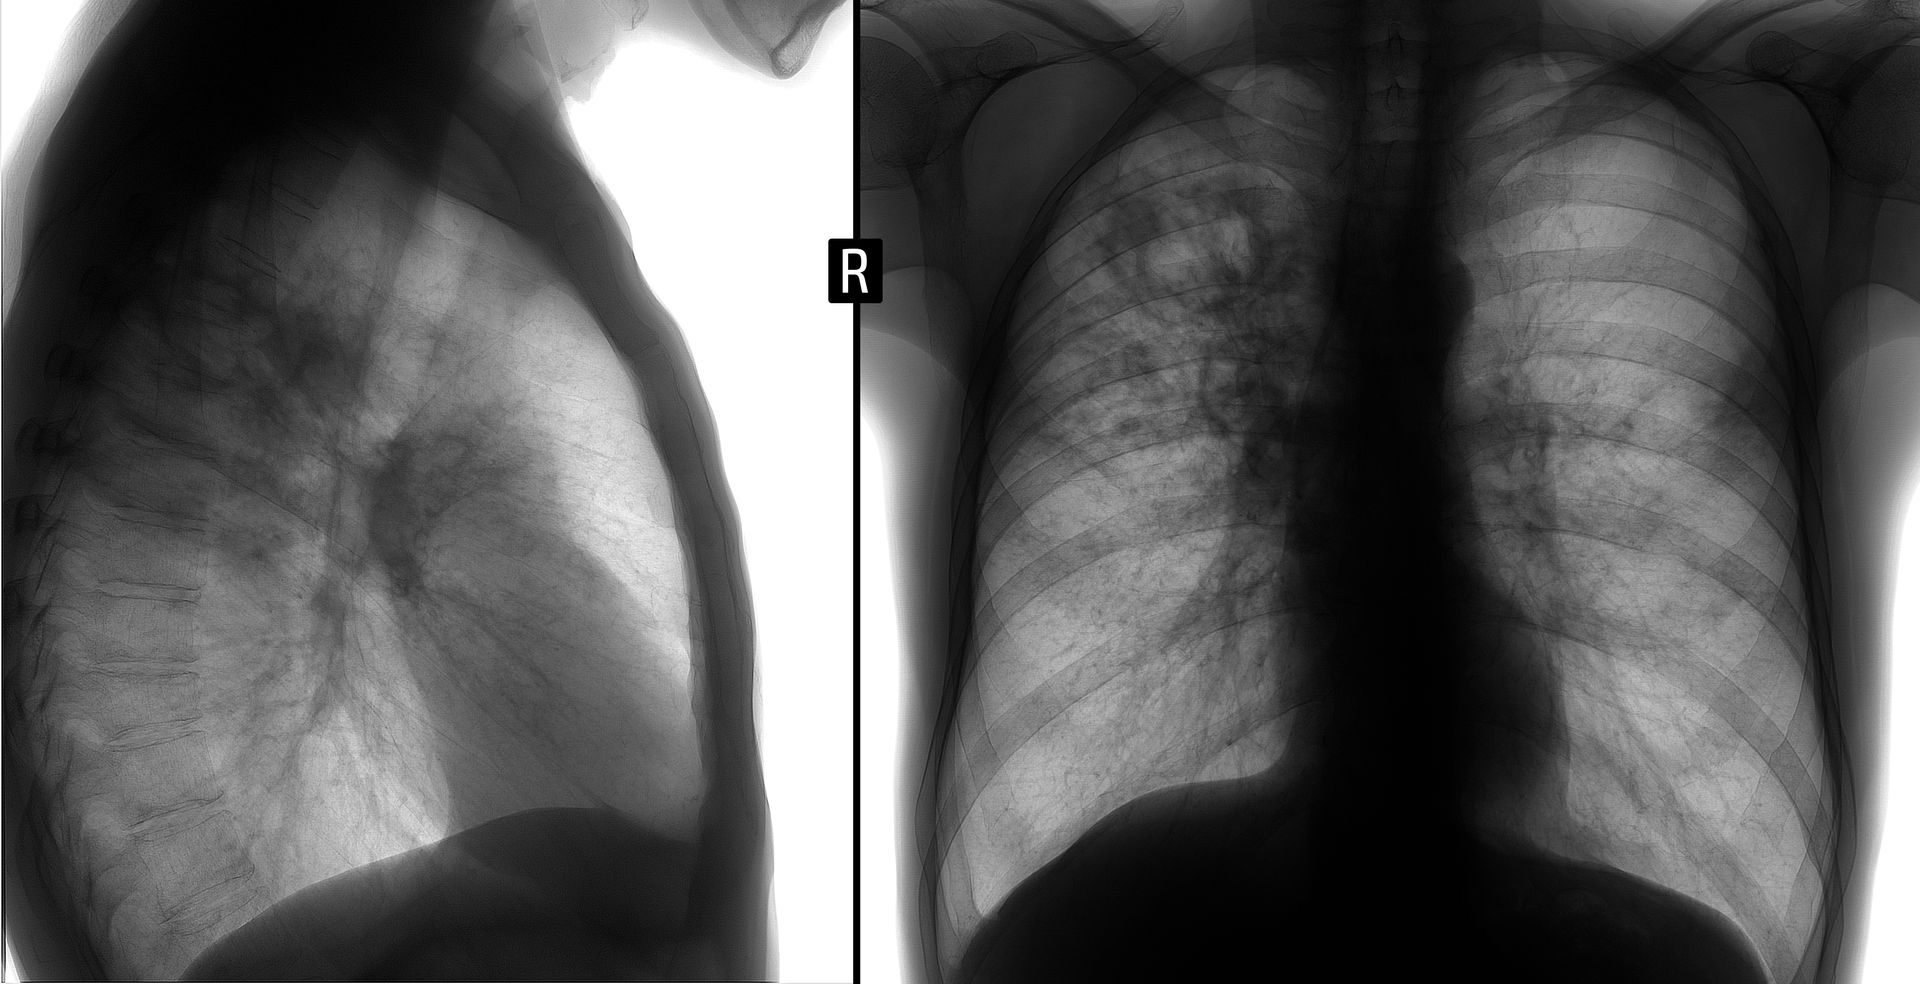

- Chest X-ray

A normal chest X-ray and no symptoms typically indicate latent TB.